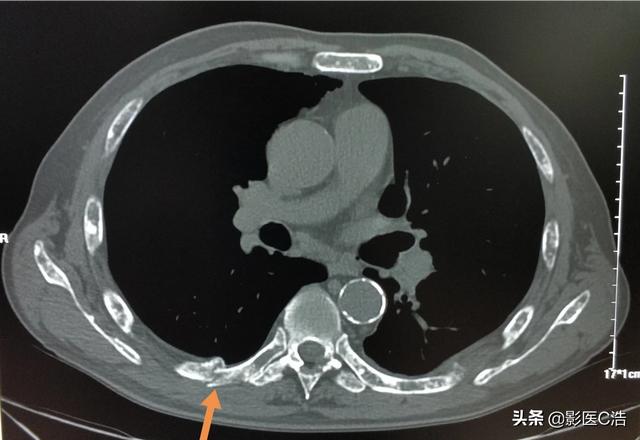

Es handelt sich um einen 58-jährigen schwulen Mann, der bei einer leichten Streckung seiner Schulter anhaltende Schmerzen verspürte und bei Röntgenaufnahmen hypodense Herde feststellte:

Es handelte sich um eine pathologische Fraktur, die durch geringe äußere Kräfte auf der Grundlage einer Knochenmetastase verursacht wurde. Es wurde eine Punktion durchgeführt und die Pathologie war eine Knochenmetastase eines schlecht differenzierten Lungenadenokarzinoms.

Dieser unregelmäßige Knoten in der linken Lunge ist der Primärherd, der nur 2,6 cm groß ist. Lungenkrebs mit Knochenmetastasen wie diesem ist nicht mehr operabel. Man kann ihm nicht helfen, Lungenkrebs ist zu häufig und einige der frühen Symptome sind atypisch oder sogar symptomlos.Bei etwa 30 % der Lungenkrebse sind Symptome von Metastasen die erste Manifestation, und Metastasen werden zuerst entdeckt, bevor weiterer Lungenkrebs entdeckt wird.